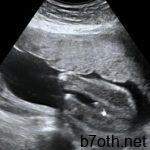

تعتمد المرأة الحامل على السونار لرؤية جنينها بعد التأكد من وجود حمل من خلال التحاليل اللازمة لذلك ، والسونار هو أحد أهم الطرق العلمية الحديثة التي تُظهر الجنين وتكشف عن نبضاته بعد مدة معينة من الحمل ، ولكن قد يحدث في بعض الأحيان عدم ظهور الجنين في السونار ويصبح الأمر مُقلقًا إذا طالت مدة الحمل ولم يظهر الجنين ، ويثير ذلك العديد من التساؤلات أهمها متى يظهر كيس الحمل ؛ ومتى يظهر الجنين داخل كيس الحمل.

من الضروري مرور مدة معينة على التبويض للتأكد من ظهور كيس الحمل بالرحم ، ويكون ذلك عادةً ما بين الأسبوع الثالث والخامس عن طريق السونار المهبلي ، ويكشف جهاز السونار عن نبضات الجنين ما بين الأسبوع السابع والثامن من عمر الحمل ، ولكن خلال الجزء الأول من الأشهر الثلاثة الأولى قد يكون من الصعب التمييز بين الحمل المبكر والإجهاض المنسي ، ولذلك فإن السيدة الحامل تخضع عادةً لفحصين بالسونار على مدار عدة أيام من أجل استبعاد حدوث إجهاض في هذه المرحلة.